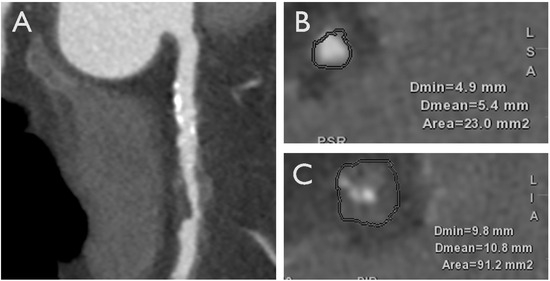

- Andreini, D.; Collet, C.; Leipsic, J.; Nieman, K.; Bittencurt, M.; De Mey, J.; Buls, N.; Onuma, Y.; Mushtaq, S.; Conte, E.; et al. Pre-procedural planning of coronary revascularization by cardiac computed tomography: An expert consensus document of the Society of Cardiovascular Computed Tomography. J. Cardiovasc. Comput. Tomogr. 2022, 16, 558–572. [Google Scholar] [CrossRef] [PubMed]

- Tajima, A.; Bouisset, F.; Ohashi, H.; Sakai, K.; Mizukami, T.; Rizzini, M.L.; Gallo, D.; Chiastra, C.; Morbiducci, U.; Ali, Z.A.; et al. Advanced CT Imaging for the Assessment of Calcific Coronary Artery Disease and PCI Planning. J. Soc. Cardiovasc. Angiogr. Interv. 2024, 3, 101299. [Google Scholar] [CrossRef]